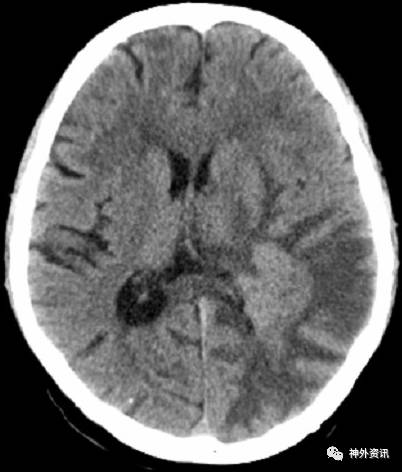

患者,男,51岁,主诉“颅内淋巴瘤术后11年余,右手乏力1月余”,我院头颅CT示:左侧顶枕骨术后改变,左侧脑室后角旁占位,伴周围脑实质水肿,考虑肿瘤复发可能(图1)。门诊以“复发性原发性中枢神经系统淋巴瘤”收入院。

图1. CT:左侧脑室后角旁占位,伴周围脑实质水肿,考虑肿瘤复发可能。